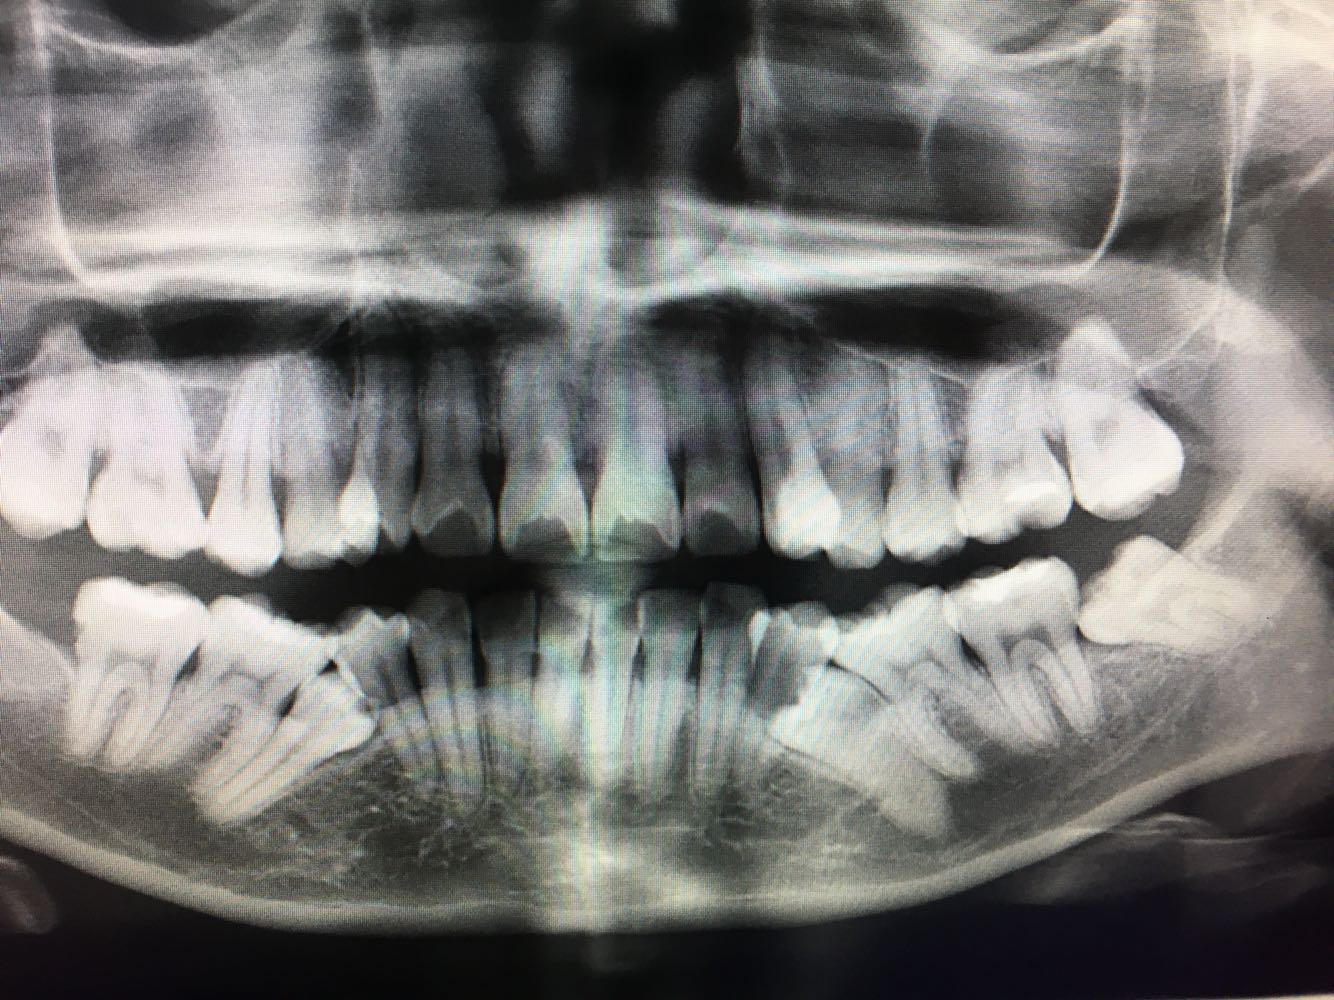

35,45口内见很小颊侧尖,其余未见 X线片示35.45阻生,余牙暂未见异常